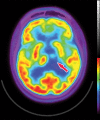

Neurodegenerative diseases are a devastating group of disorders that can be difficult to accurately diagnose. Although these disorders are difficult to manage owing to relatively limited treatment options, an early and correct diagnosis can help with managing symptoms and coping with the later stages of these disease processes. Both anatomic structural imaging and physiologic molecular imaging have evolved to a state in which these neurodegenerative processes can be identified relatively early with high accuracy. To determine the underlying disease, the radiologist should understand the different distributions and pathophysiologic processes involved. High-spatial-resolution MRI allows detection of subtle morphologic changes, as well as potential complications and alternate diagnoses, while molecular imaging allows visualization of altered function or abnormal increased or decreased concentration of disease-specific markers. These methodologies are complementary. Appropriate workup and interpretation of diagnostic studies require an integrated, multimodality, multidisciplinary approach. This article reviews the protocols and findings at MRI and nuclear medicine imaging, including with the use of flurodeoxyglucose, amyloid tracers, and dopaminergic transporter imaging (ioflupane). The pathophysiology of some of the major neurodegenerative processes and their clinical presentations are also reviewed; this information is critical to understand how these imaging modalities work, and it aids in the integration of clinical data to help synthesize a final diagnosis. Radiologists and nuclear medicine physicians aiming to include the evaluation of neurodegenerative diseases in their practice should be aware of and familiar with the multiple imaging modalities available and how using these modalities is essential in the multidisciplinary management of patients with neurodegenerative diseases.©RSNA, 2020.